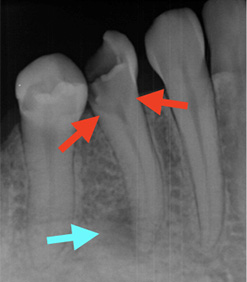

ただし、むし歯の進行の深さと、歯髄の炎症の程度は比例するとは限りません。なぜなら、歯髄には細菌の進行を防ぐ防御機能が備わっているからです。特に大人のむし歯でゆっくり進行したものは、「むし歯が大きいのに痛くない」といったことも起こりえます。

したがって、レントゲンによる判断だけではなく、種々の検査を総合的に判断してからの治療になります。

歯髄温存療法の適応は歯髄の炎症が「ない」もしくは「部分的」なものに限られます。